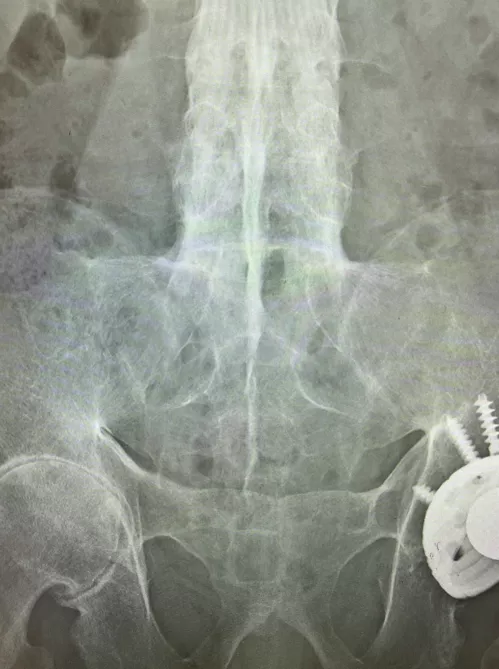

皮膚には爪異常や乾癬を認めない。末梢関節に腫脹圧痛なし。指炎なし。アキレス腱付着部の腫脹圧痛なし。両側仙腸関節に圧痛あり。Schober試験で5㎝以下であり腰椎可動域制限あり。血液検査ではCRP1.85mg/dL、赤沈34mm/hr、リウマトイド因子陰性、抗CCP抗体陰性、抗核抗体陰性であった。便潜血2回陰性。単純X線骨盤正面像を示す(写真1)。

写真1 単純X線 骨盤正面像